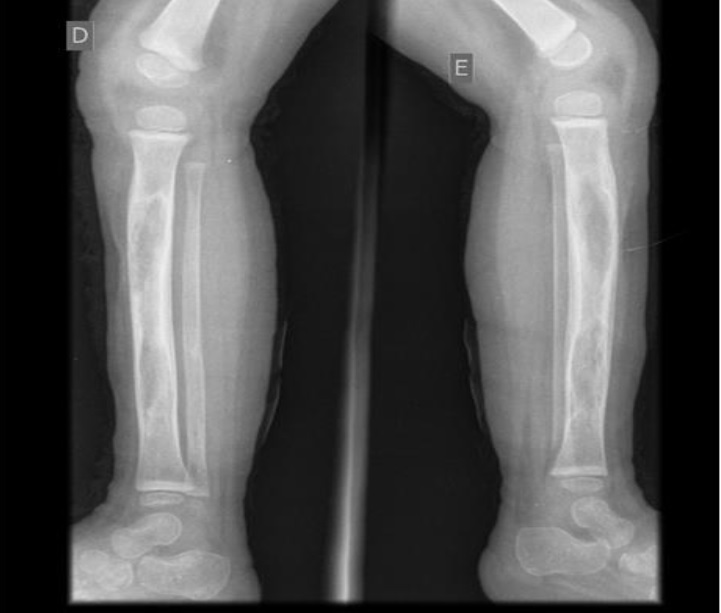

Em ultrassonografia de membros inferiores, foram confirmados abscessos nos pés. Na investigação, foi diagnosticada a osteomielite que acometia úmero, tíbia, ossos dos pés e das mãos bilateralmente. Foi feita drenagem contínua de lojas de secreção purulenta na região das tíbias.

As radiografias confirmaram o diagnóstico de osteomielite (Figuras 1 a 5). Em culturas de secreção tibial, foram isolados Escherichia coliESBL e Proteus mirabilis, sensíveis a imipenem e amicacina. Dessa forma, optou-se por tratamento com antibioticoterapia parenteral, ao longo de tempo prolongado de internação.

Foram realizadas radiografias seriadas e o consequente tratamento cirúrgico de drenagem de abscessos e colocação de drenos. Não foram realizadas cintilografias e ressonância magnética, uma vez que o diagnóstico se fez tardiamente com o quadro já instalado de forma importante. Esses últimos exames contribuiriam para um diagnóstico mais precoce. Não foi realizada biópsia óssea das áreas acometidas, exame eventualmente necessário1. Em alguns casos, radiografias podem estar normais4, porém, em outros, como no caso descrito, elas se apresentam alteradas, conforme visto nas imagens.

Em seguimento ambulatorial, o paciente apresenta padrão radiológico melhor, como evidenciado em radiografia recente, ausente o atraso no crescimento, uma vez que placas epifisárias não se mostram afetadas. Permaneceu em antibioticoterapia estendida por mais cinco meses além do programado na alta hospitalar e isento de complicações novas por osteomielite. Internações devido às crises álgicas ou outros tipos de infecções já foram registradas.